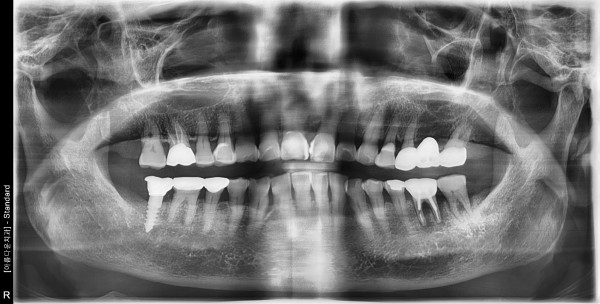

85세여자 하악좌측구치부 뼈이식및임플란트식립